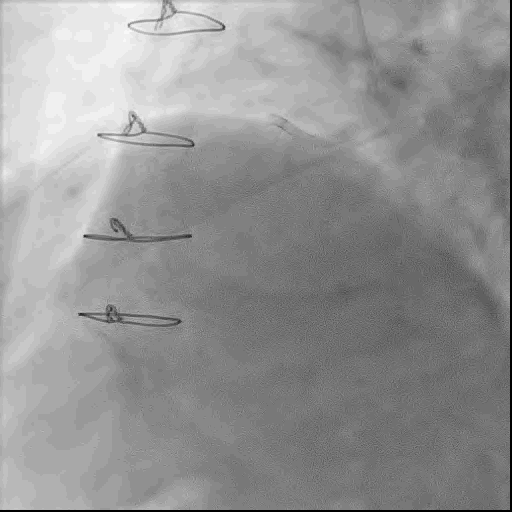

首先置入Cosair135微导管,使用XTR导丝反复尝试无法通过闭塞段,更换UB3导丝后成功通过闭塞段。

冠脉造影提示RCA闭塞钙化负荷较重,使用球囊锚定技术,小球囊反复扩张闭塞病变。

后更换微导管送入RCA中远段,并更换工作导丝至左室后支远端。

术中,球囊扩张RCA中远段后出现夹层,使用球囊压迫后复查造影TIMI血流3级,故结束手术。